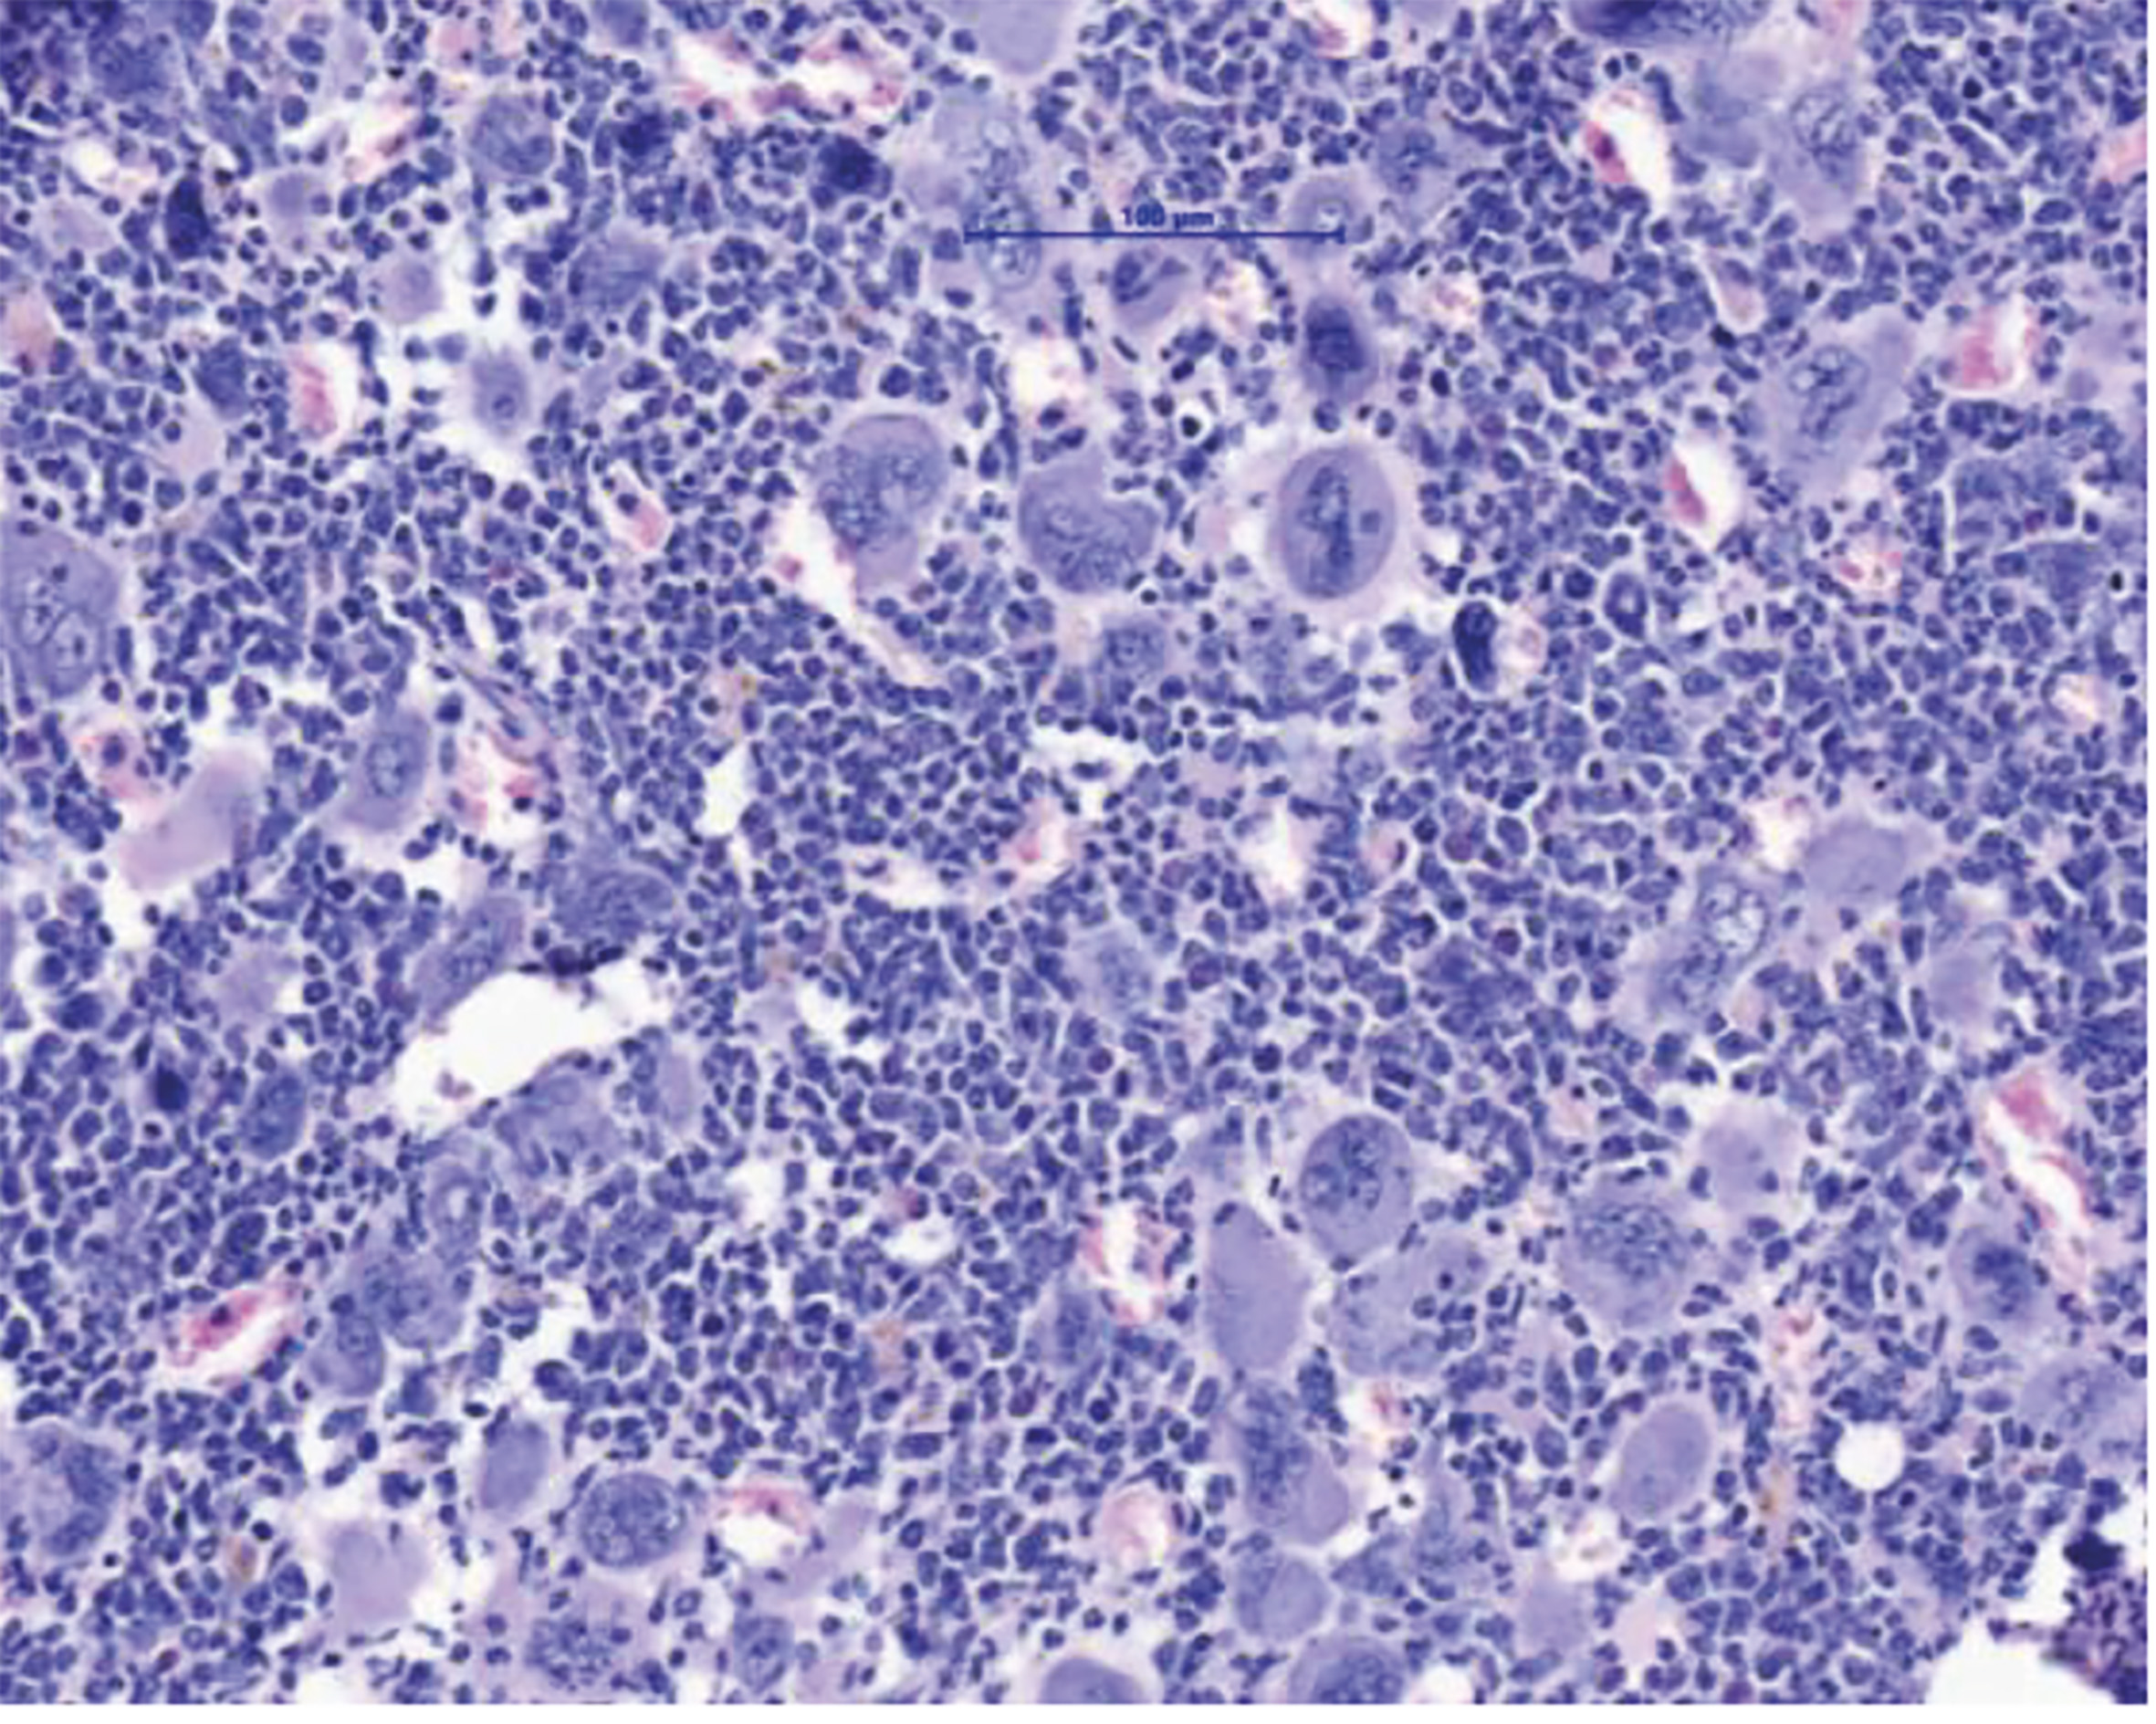

MPN sind durch eine Expansion des blutbildenden Systems im Knochenmark charakterisiert. Dies führt zum Anstieg verschiedener Zellreihen und im Endzustand dann zur Knochenmarksvernarbung und auch akuten Leukämie. (Grafik: MUI/Univ-Klinik für Innere Medizin V)

Innsbruck, Bonn am 2.12.2025: Myeloproliferative Neoplasien (MPN) sind Blutkrebserkrankungen, die durch eine Überproduktion von Blutzellen gekennzeichnet ist. Diese Erkrankungen treten in der Regel ab einem Alter von 60+ Jahren auf und können über lange Zeit gut kontrolliert werden. Gefährlich werden MPN vor allem nach dem Übergang in eine Myelofibrose – eine lebensbedrohliche Vernarbung des Knochenmarks. Eine allogene Stammzelltransplantation bietet für die betroffenen Patient:innen bis heute die einzige Aussicht auf Heilung. „Wir brauchen dringend neue Therapiekonzepte. Eine Stammzell-Transplantation ist für viele Patient:innen aufgrund ihres hohen Alters oder wegen Begleiterkrankungen mit zu hohen Risiken verbunden“, erklärt Dominik Wolf, Direktor der Univ.-Klinik für Innere Medizin V (Hämatologie und Onkologie) an der Medizinischen Universität Innsbruck, den Hintergrund einer soeben im Fachjournal Nature Communications hochrangig publizierten Forschungsarbeit, die er konzipiert und gemeinsam mit Lino Teichman und Miriam Körber vom UKBonn durchgeführt hat. „Wir zeigen in dieser Arbeit ein mögliches neues Therapiekonzept auf, das man klinisch weiterentwickeln sollte“, sagt Wolf, der gemeinsam mit Lino Teichmann als Letzt- und korrespondierender Autor firmiert. Den Wissenschafter:innen ist es gelungen, das NLRP3-Inflammason im Tiermodell zu hemmen und dadurch deutliche Verbesserungen des Krankheitsverlaufs zu erzielen: Die Knochenmarksvernarbung und die Milzvergrößerung bildeten sich zurück und das Blutbild verbesserte sich.

Konkret haben sich die Autor:innen mit den Mechanismen der Entzündungsreaktion bei MPN beschäftigt, da diese zu vielen klinischen Symptomen und letztlich auch zur Vernarbung des Knochenmarks führt. Das NLRP3-Inflammasom ist ein Sensor für Gefahrensignale, der Entzündungsprozesse im Körper steuert und dessen Bedeutung bereits eingehend bei chronischen Entzündungserkrankungen wie Atherosklerose, Gicht oder auch Diabetes Typ-2 studiert wurde. Bei MPN wird die Entzündung in den bösartigen, aber auch in den begleitenden, noch gesunden Blutzellen von einer genetischen Treibermutation ausgelöst, wobei hier die aktivierende Mutation JAK2V617F eine zentrale Rolle spielt.

„Wir haben uns erstmalig damit beschäftigt, welche funktionelle Rolle das NLRP3-Inflammasom für die Entzündungsreaktion bei myeloproliferativen Neoplasien hat“, sagt Erstautorin Ruth-Miriam Körber vom Universitätsklinikum Bonn. Dafür haben die Mediziner:innen in Zusammenarbeit mit der German Study Group of MPN (GSG-MPN) eine große Anzahl von Proben ausgewertet und die Entzündungsreaktionen kartiert, bevor sie anhand unterschiedlicher Techniken die Aktivierung des NLRP3-Inflammasoms bei den Patient:innen und auch im MPN-Tiermodell nachweisen konnten.